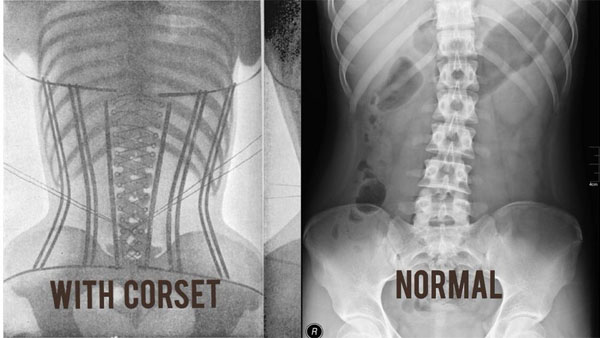

Nak tahu betapa bahaya pemakaian bengkung kerengga ke atas badan korang?

Pemakaian corset menyebabkan anda menekan bahagian pertengahan badan yang boleh menyebabkan perut anda ke atas dan peluang untuk anda mengalami pedih ulu hati dan tidak penghadaman adalah tinggi. Bayangkan lama-lama nanti boleh kena ulser.

3. PERNAFASAN

Bila pakai corset, nak bernafas pun susah. Bayangkan diaphragm (anak panah hijau) susah nak mengembang. Jadinya kurang oksigen masuk dalam badan korang.